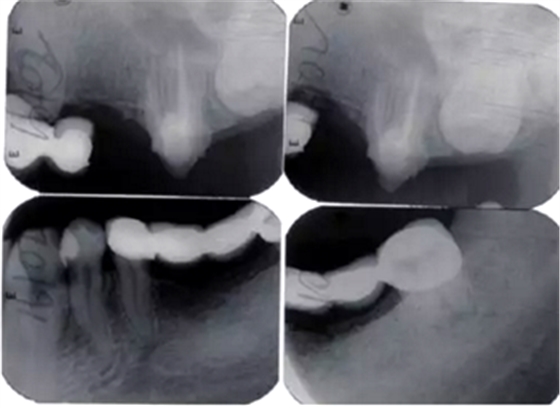

術后2周進行重新牙體預備,制作并戴入臨時修復體,牙齦塑形(圖6)。術后3個月,上前牙牙齦形、線、點位置基本穩(wěn)定,進行永久修復。上頜采用烤瓷固定橋修復,樁核冠單冠修復,下頜固定-活動義齒修復,恢復良好的牙齒外形和接觸區(qū)、重建完整牙列、恢復口腔功能、改善美學效果(圖7)。